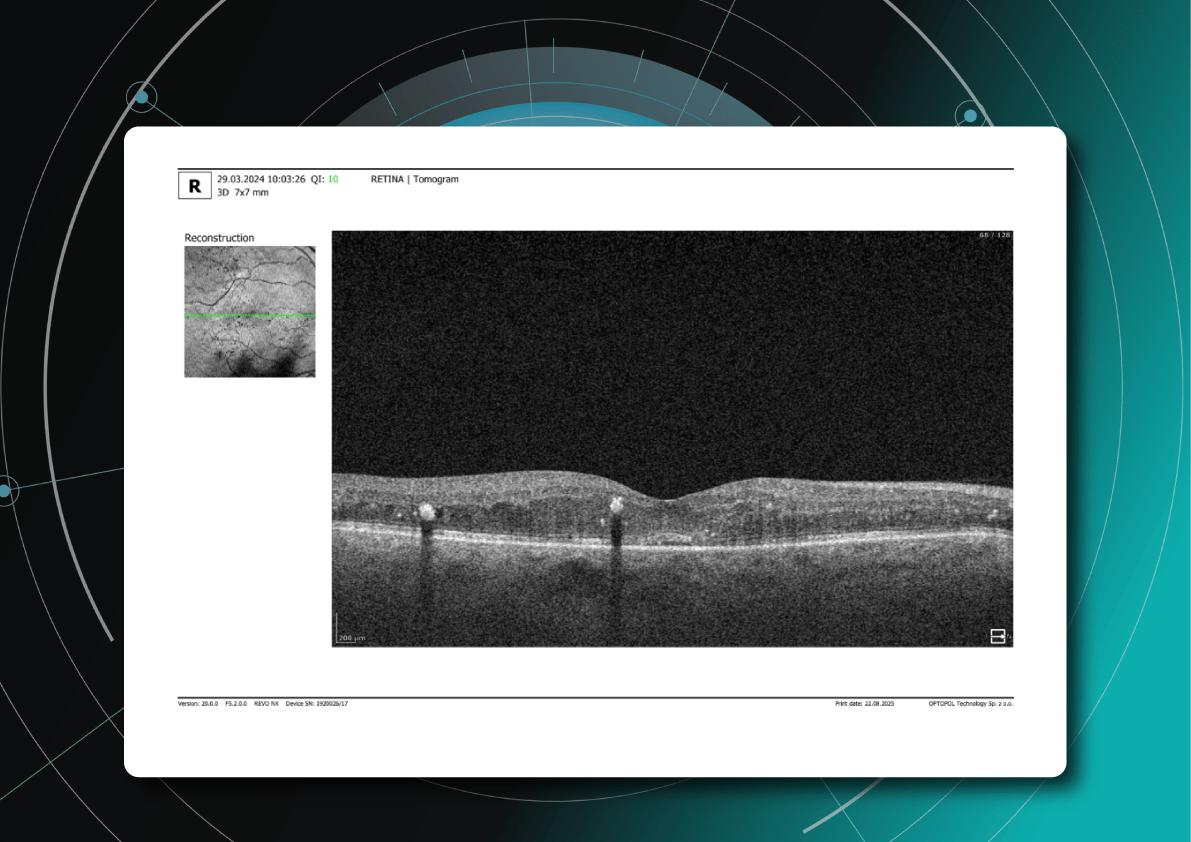

For instance, AI today can assess the early risk of glaucoma based on the GCC asymmetry measurements. Here is how AI-powered OCT workflow would look.

AI-assisted readings of OCT scans are already helping not only with pathology detection but also with the analysis of its progression or response to treatment. This represents a new approach to monitoring, where practitioners no longer need to sift through various patient notes but can directly compare reports from previous examinations and observe how, for instance, shadowing has changed in micrometers.

These concerns primarily revolve around glaucoma, age-related macular degeneration (AMD), and diabetic retinopathy (DR). AI can help identify these and other eye diseases at their earliest stages during routine visits. Some retinal changes are so minute that they escape detection by the human eye, making the program’s ability to detect tiny retinal changes invaluable.

Another significant benefit of AI systems lies in their approach to OCT analysis for glaucoma. Traditional methods rely on normative databases to assess retinal normality, but these databases are often limited in size and represent a select group of individuals. This can result in missed diagnoses of early glaucoma in those who deviate from the “norm” or unnecessary referral from optometry to ophthalmology for those who don’t fit the “normal” profile but have healthy eyes. AI can overcome this limitation by providing more personalized and comprehensive analysis.

Glaucoma risk evaluation

Millions risk irreversible vision loss due to undiagnosed glaucoma, underscoring the need for improved early detection. Current tests often rely on observing changes over time, delaying treatment assessment and hindering early identification of rapid disease progression. OCT frequently detects microscopic damage to ganglion cells and thinning across these layers before changes are noticeable through other tests. However, the earliest signs on the scan can still be invisible to the human eye.

AI algorithms offer insights into glaucoma detection by routinely analyzing the ganglion cell complex, measuring its thickness, and identifying any thinning or asymmetry to determine a patient’s glaucoma risk without additional clinician effort.

Another significant benefit of AI systems is that OCT for glaucoma usually utilizes a normative database to assess retinal normality. However, these databases are limited in size and represent an average of a select group of people, potentially missing early glaucoma development in those who deviate from the “norm.” Conversely, individuals may be unnecessarily referred for treatment due to not fitting the “normal” profile, even if their eyes are healthy.